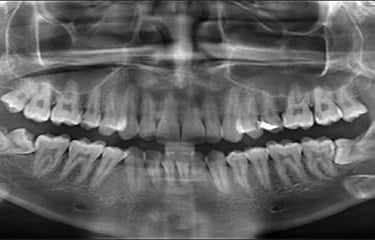

OPG and RVG are digital dental X-rays that give clear and detailed images of your teeth and jaw. They help in accurate diagnosis and allow the dentist to plan safe and effective treatment.

OPG and RVG